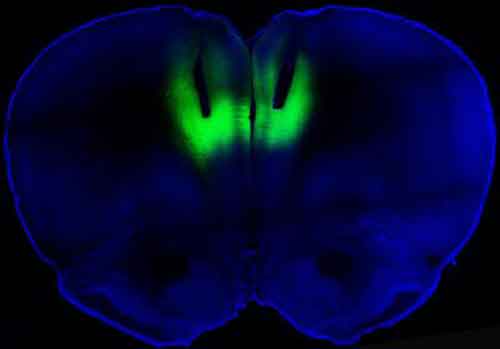

Gli innovativi esperimenti sono stati eseguiti su modelli animali e gli scienziati hanno reso un gruppo di ratti severamente dipendenti alla cocaina. Poi hanno misurato l’attivita” cerebrale della loro corteccia frontale (porzione prelimbica) che e’ un’area del cervello importantissima per quello che riguarda la capacita’ del soggetto di prendere decisioni e di controllare i propri comportamenti. Gli scienziati hanno osservato che tale corteccia frontale viene “spenta” dalla somministrazione cronica e compulsiva di cocaina e quindi i soggetti hanno meno capacita’ di controllo del loro comportamento e dell’assunzione di droga. Utilizzando l’optogenetica, i ricercatori hanno messo a punto una tecnica che riesce a “risvegliare” la corteccia frontale inibita dalla cocaina, grazie ad un virus speciale che riesce a riattivare in modo selettivo i neuroni della zona del cervello prescelta. In seguito a tale riattivazione dei neuroni “addormentati”, il comportamento di assumere droga in maniera compulsiva e quindi la dipendenza scompare. “Le implicazioni di questo studio sono importantissime e di immediata utilita’ terapeutica” commenta il Prof. Bonci. [one_fourth last=”no”]